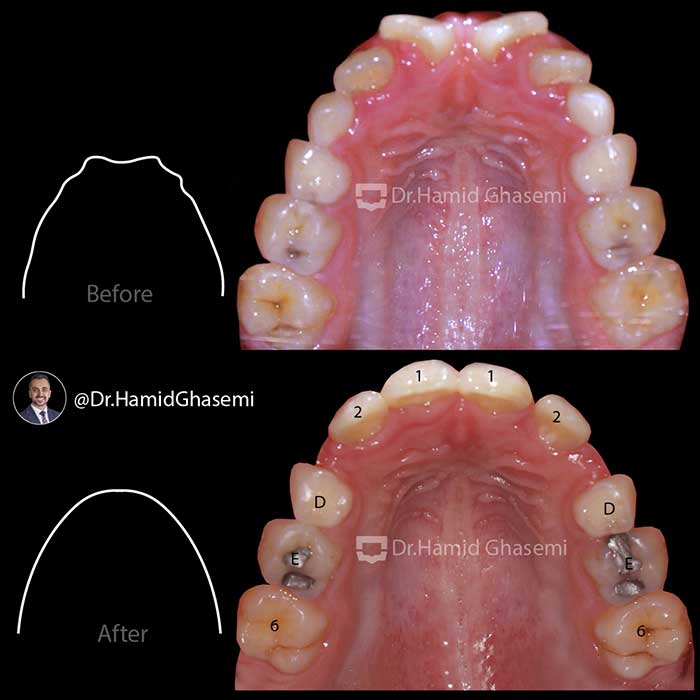

دیستالیزیشن (عقب بردن) فک بالا در پسر ۱۰ ساله با فک بالای جلو زده با استفاده از دستگاه هدگیر و درمان ثابت 2×4 جهت مرتب کردن دندانهای قدامی. به تغییرات حالت لب بالا بعد از دیستالیزیشن فک بالا دقت کنید.

Upper arch distalization in 10 years old boy with prognathic maxilla using headgear and 2×4 fixed braces to level and align front teeth. Attend to the upper lip posture after upper arch distalization